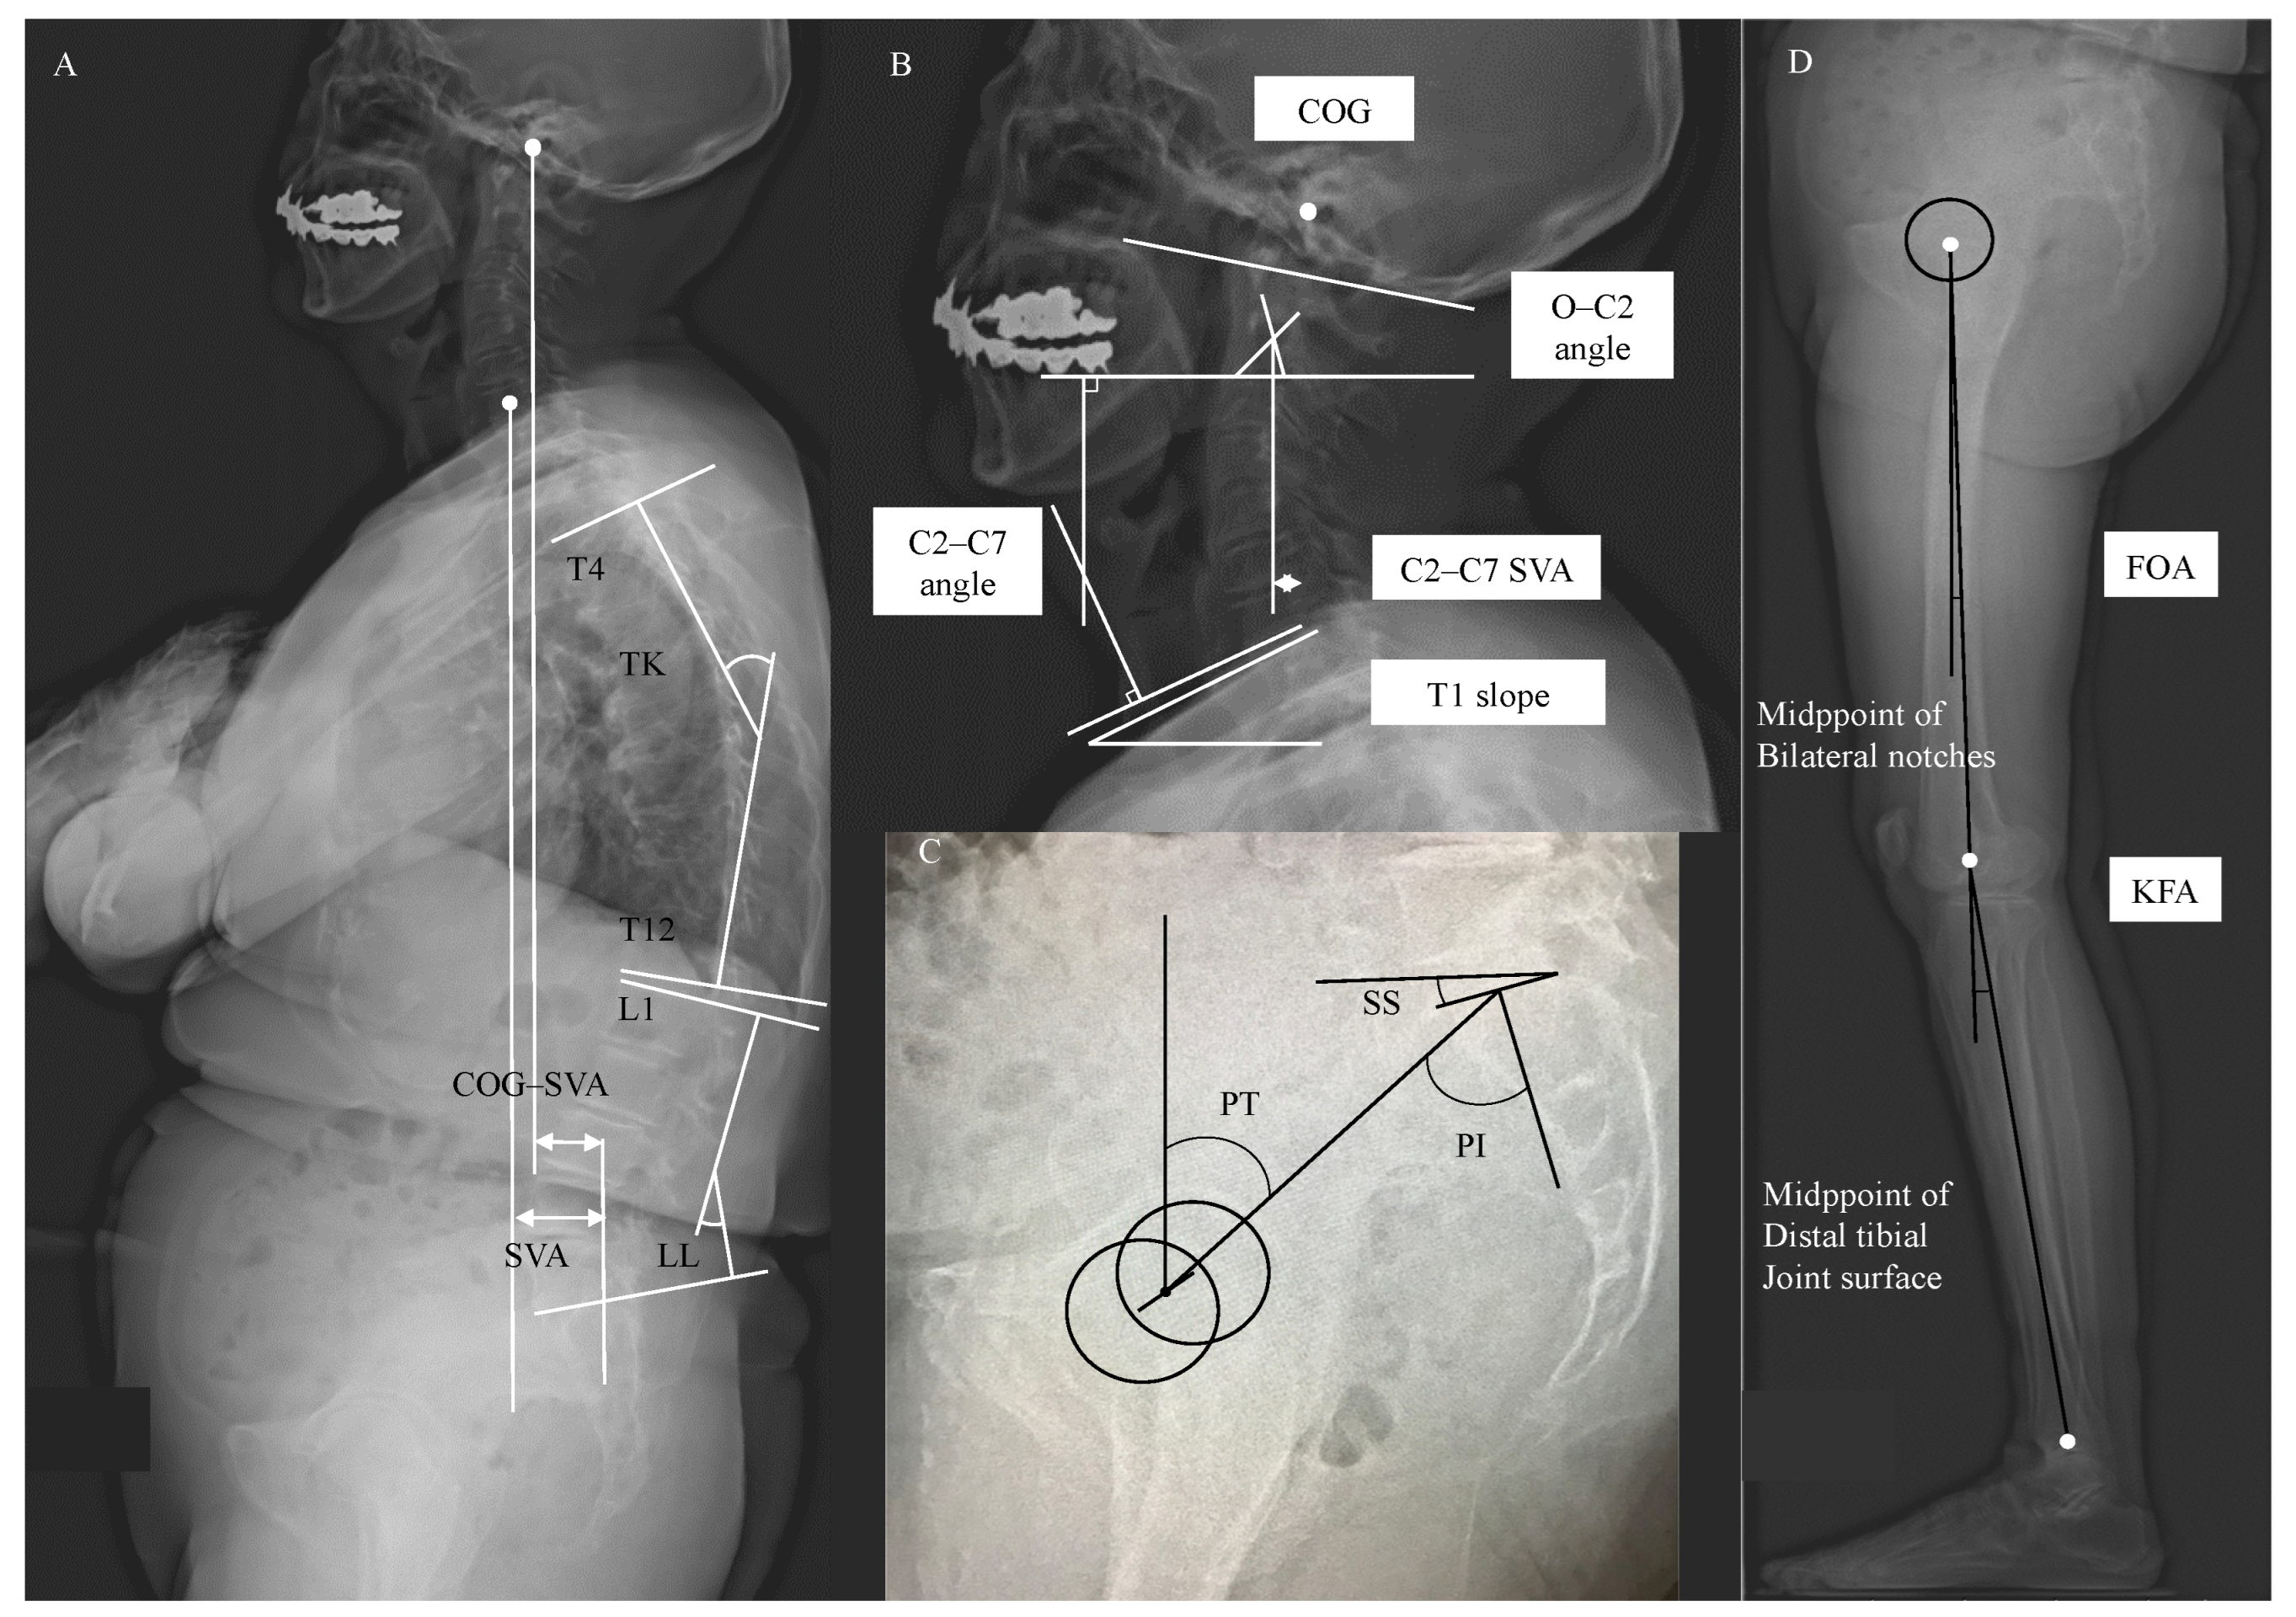

2.2. Image Acquisition and Anatomical Parameters Extraction

| O–C2 angle (°) | 12.3 ± 7.6 (0–28) |

| C2–C7 angle (°) | 21.2 ± 11.0 (6–42) |

| C2–C7 SVA (mm) | 21.0 ± 8.0 (7.6–38.7) |

| COG–SVA (mm) | 86.3 ± 55.6 (15–224.7) |

| T1 slope (°) | 29.4 ± 11.6 (12–58) |

| TK (°) | 36.4 ± 15.2 (12–67) |

| LL (°) | 38.2 ± 15.8 (15–69) |

| PT (°) | 24.5 ± 8.7 (12–47) |

| SS (°) | 27.8 ± 6.7 (13–38) |

| PI (°) | 52.9 ± 9.5 (30–65) |

| PI−LL (°) | 10.9 ± 19.5 (−23–41) |

| SVA (mm) | 66.1 ± 52.5 (4–162) |

| FOA (°) | 5.8 ± 3.0 (0–13) |

| KFA (°) | 8.5 ± 4.5 (0.3–18) |